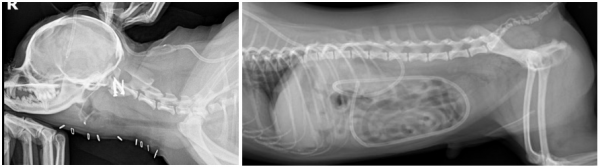

94e62ed5723a30503d8471b780ac418b_1759112163_1058.jpg

94e62ed5723a30503d8471b780ac418b_1759112173_5799.png

1. VP Shunt (Ventriculoperitoneal Shunt) 삽입

: 과도한 뇌척수액(CSF)을 복강으로 우회 배출시켜 뇌압을 낮추는 수술

94e62ed5723a30503d8471b780ac418b_1759112185_9051.png

2. AAI 고정 수술

: 경추의 불안정 부위를 고정하여 척수 압박을 해소하고 신경 손상을 예방하는 수술

94e62ed5723a30503d8471b780ac418b_1759112193_5817.png

AAI 수술 후 핀과 레진이 삽입된 모습 (좌) , VP shunt 수술 후 복강 내로 카테터가 삽입되어 있는 모습 (우)